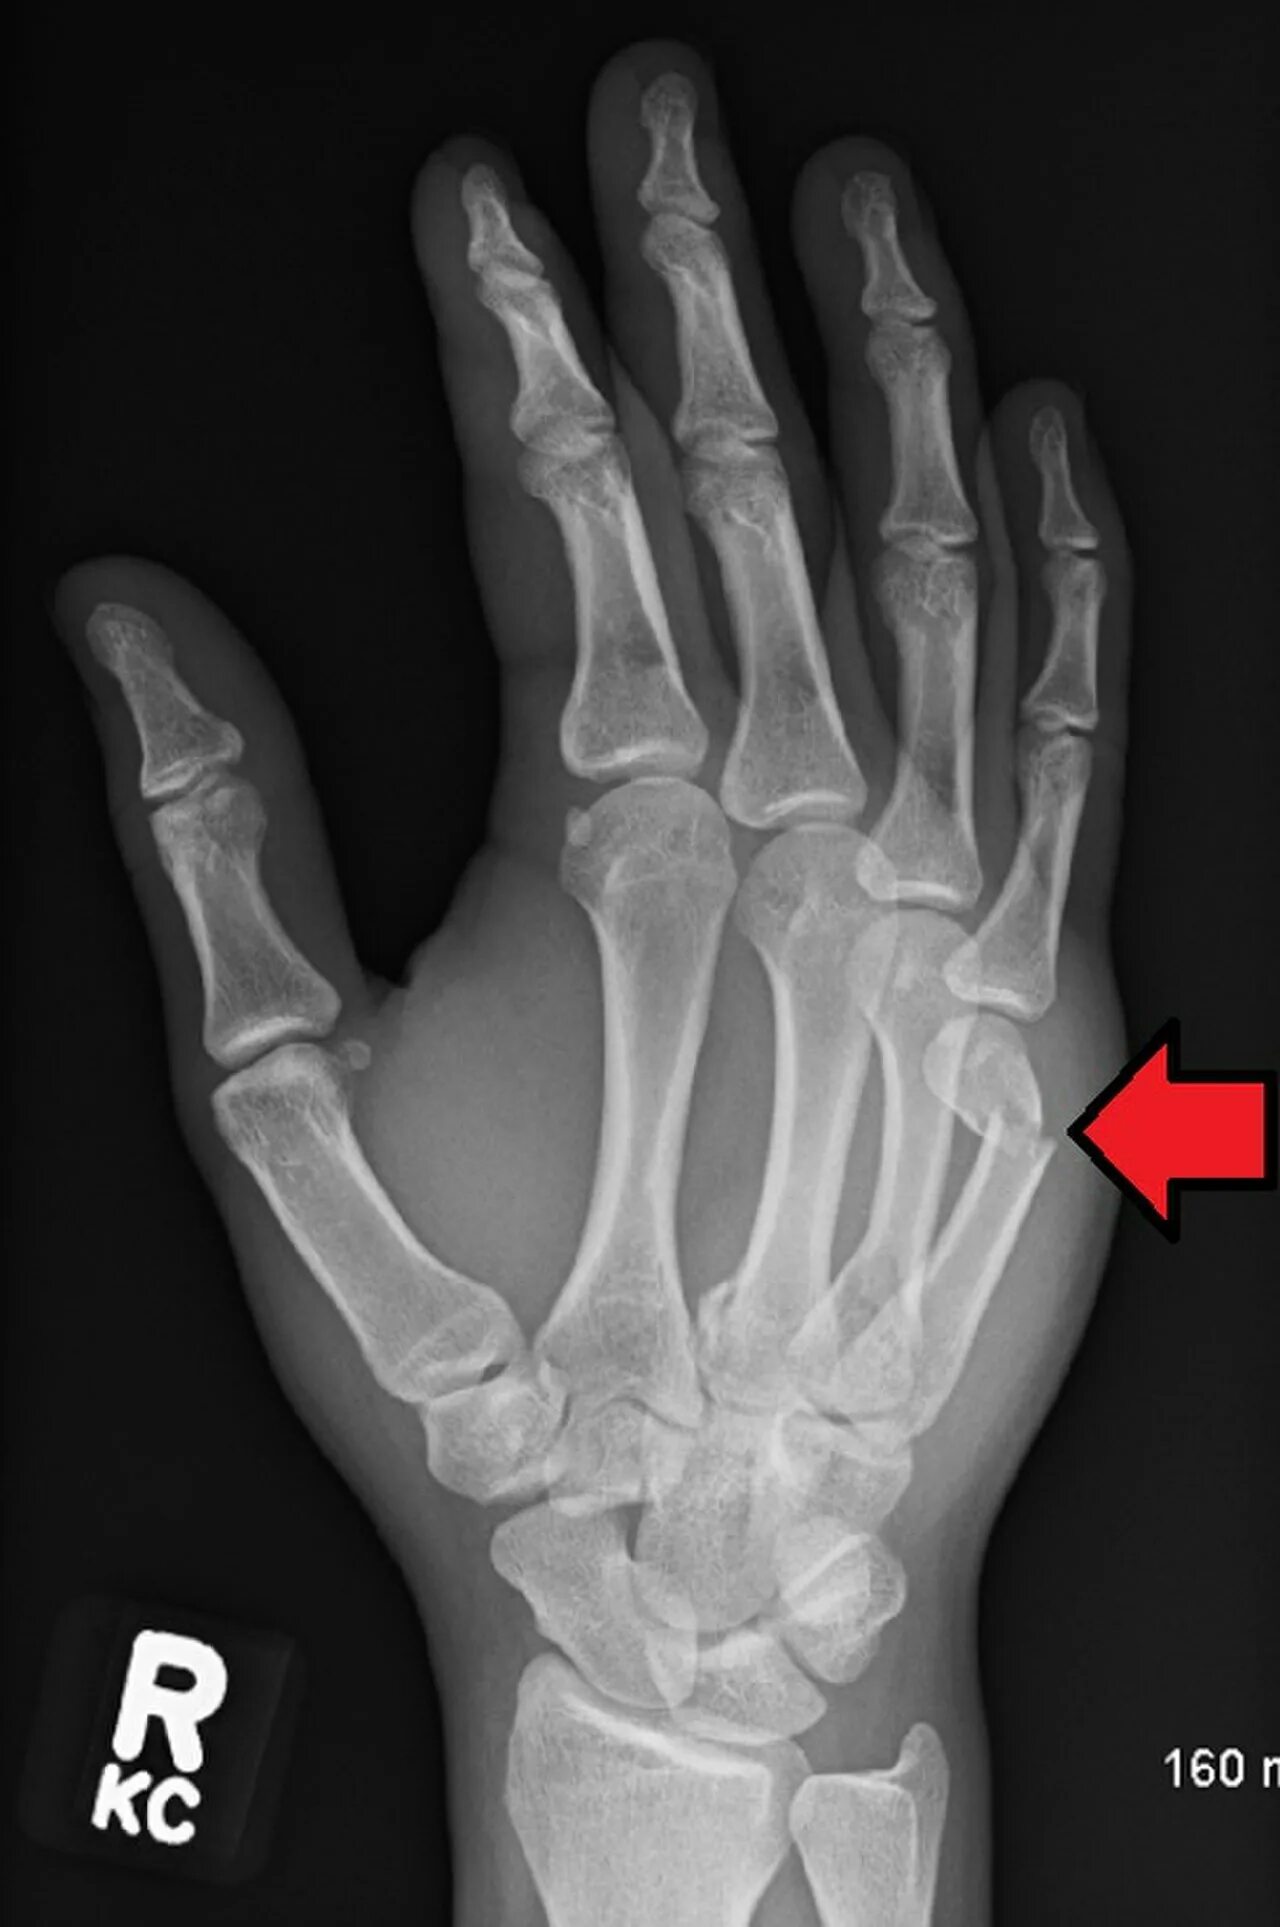

Перелом пятой пястной кости